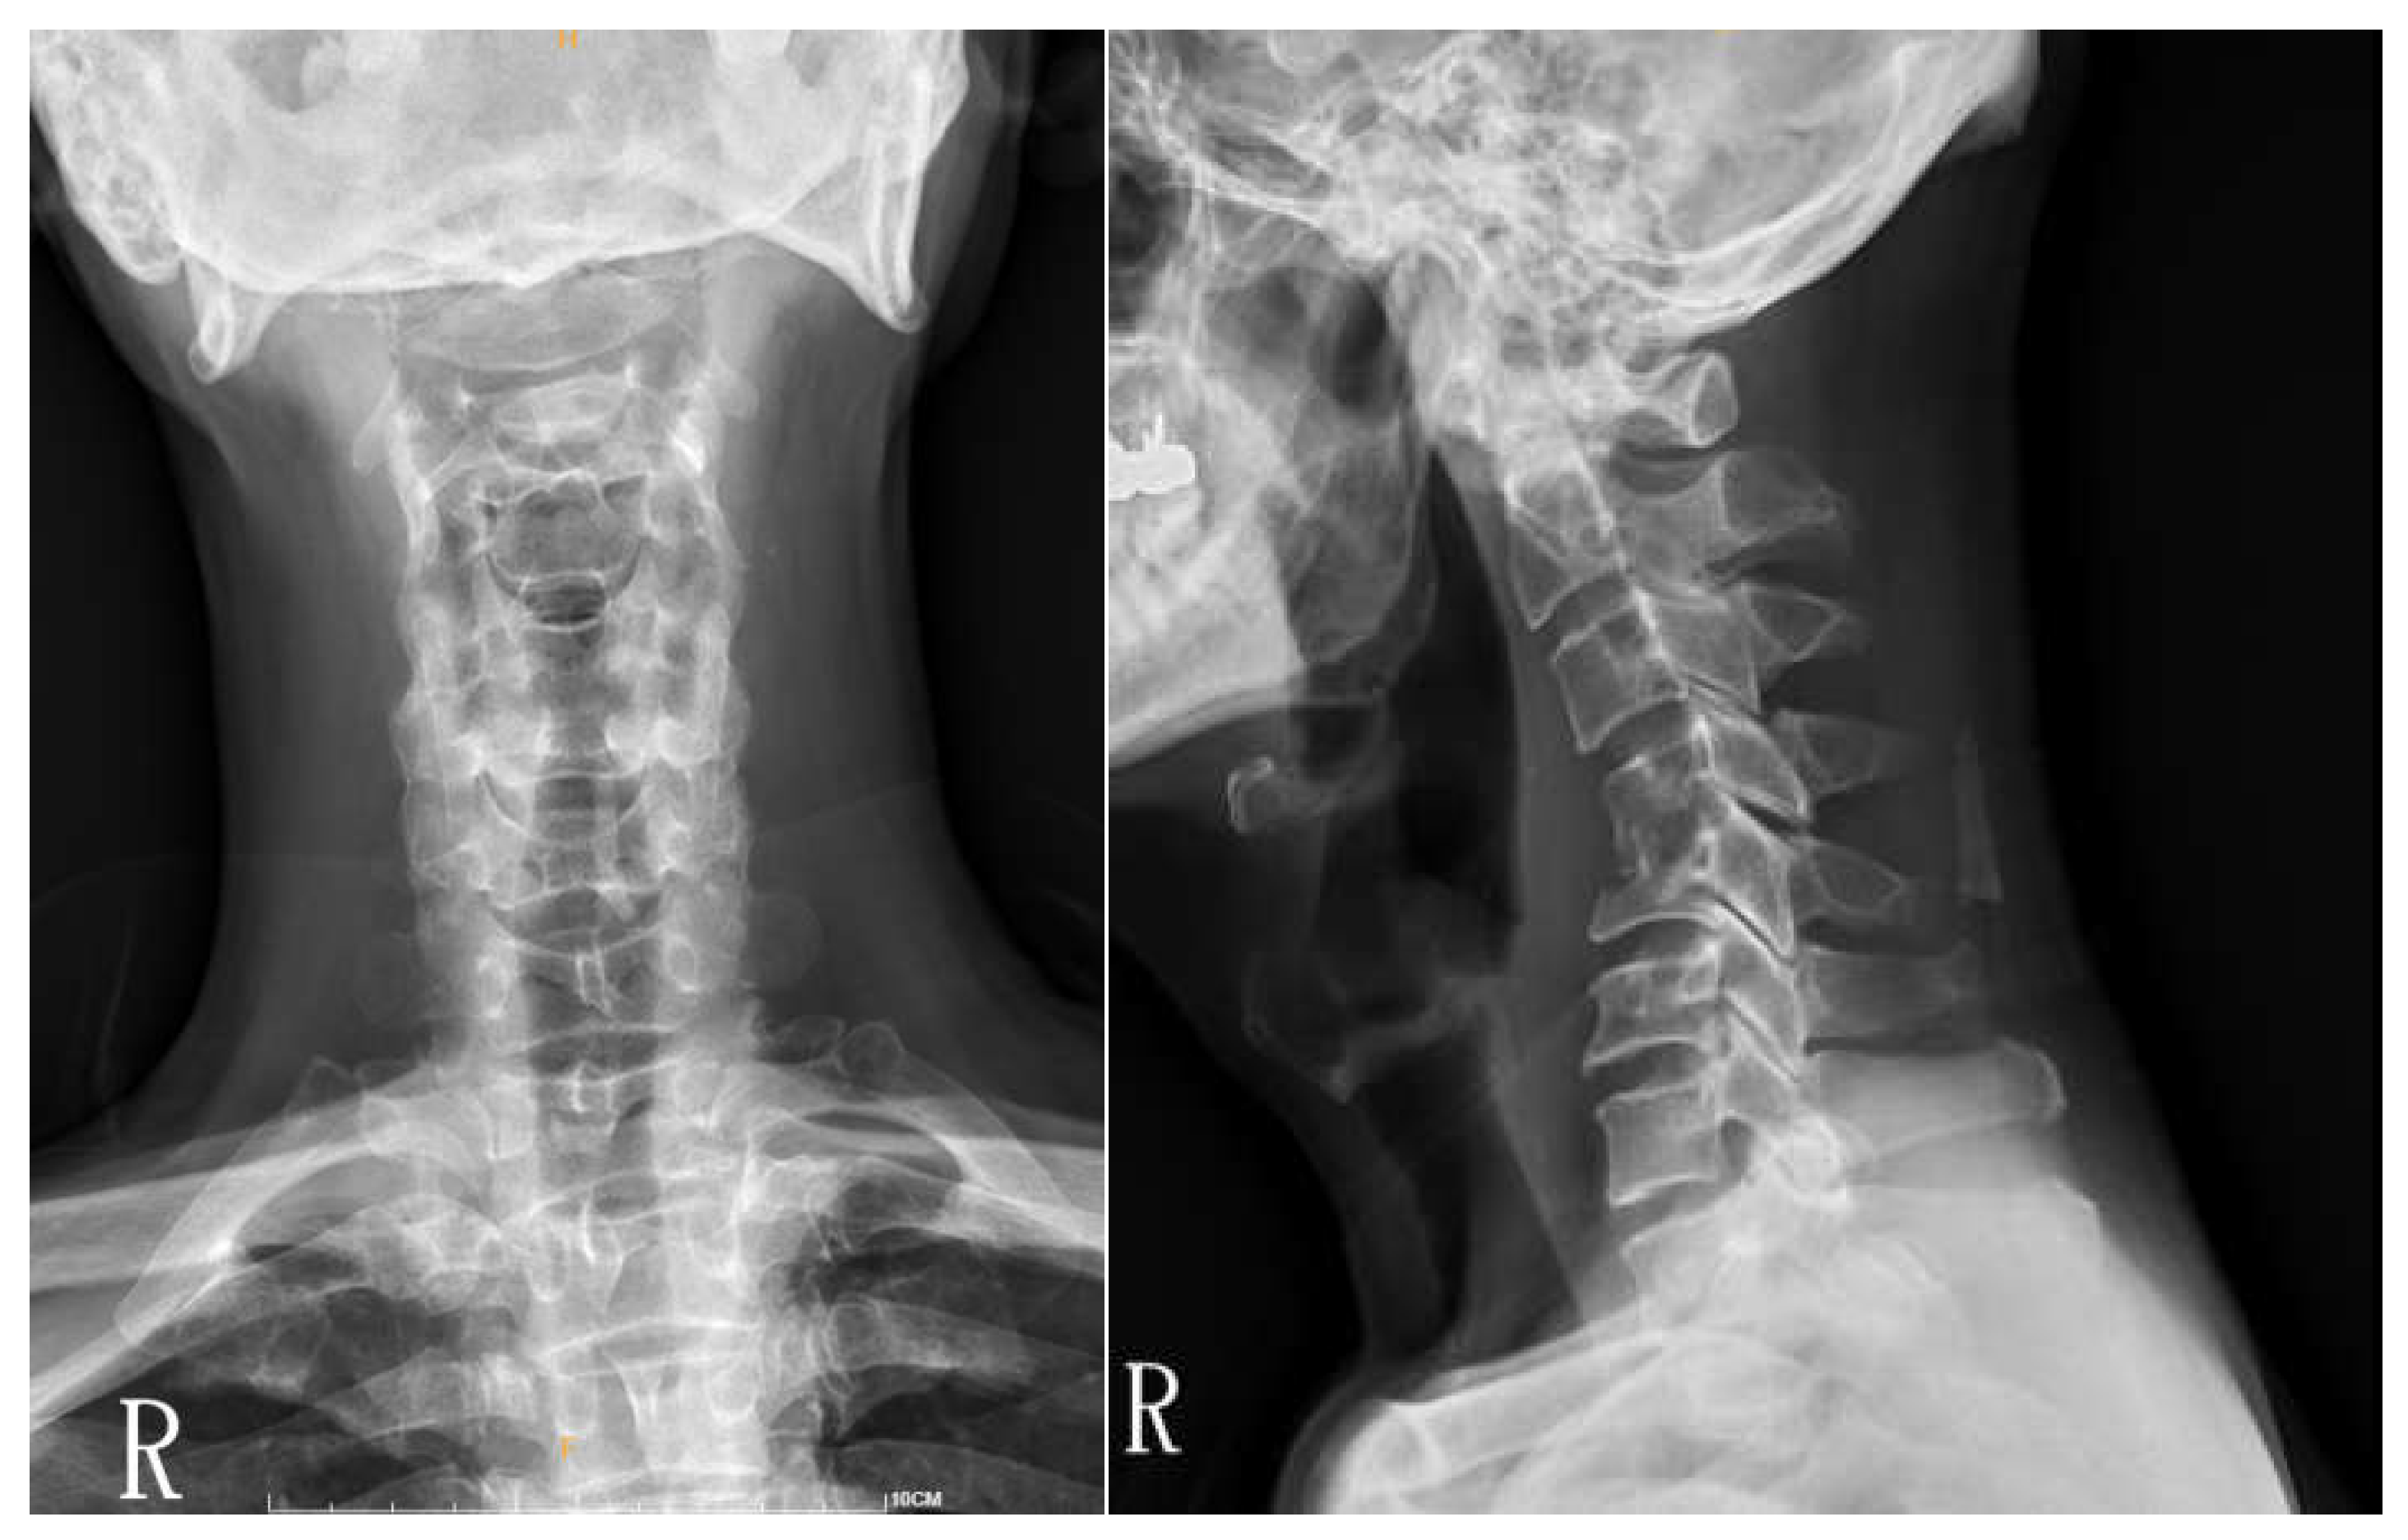

Figure 1. Cervical spine x ray of C4/5 spondylodiscitis with mild osteolytic change and compression fracture(s) at the C4-5 level. Mild widening of the retropharyngeal space around the C4-5 level was noted.

Figure 3. After anterior C5 corpectomy and reconstruction with trabecular metal (TM) cage and cervical plate and cervical discectomy of C4/C5 and C5/C6. Cervical spine AP and lateral views show normal alignment with intravertebral implant at C5 and anterior metal fixation at C4-C6. Mild edge spur formation is noted at C3 and C6.